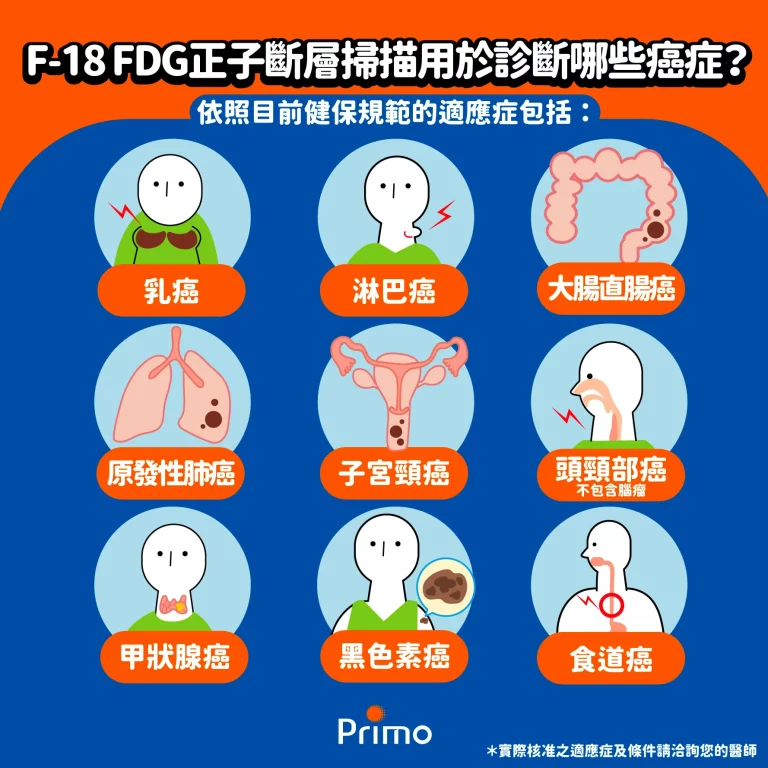

正子造影(PET-CT)最常配合使用的藥物是放射性氟化去氧葡萄糖(F-18 FDG),利用F-18 FDG在特定器官與組織代謝情形,提供精準的全身診斷報告,譬如癌細胞愛吃糖的特性

氟化去氧葡萄糖(F-18 FDG)用在哪些疾病?

「放射性氟化去氧葡萄糖(fluorodeoxyglucose;以下簡稱:F-18 FDG)」是一種核醫/正子放射性藥物,更是正子斷層造影(PET-CT)不可或缺的靈魂角色。